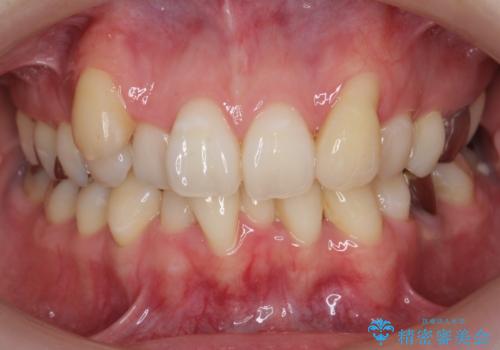

前歯のがたつきをなおしたい マウスピース矯正

担当医 大元洋佑

![[ マウスピース矯正 ] 前歯の角度・がたつきを治したい。の症例 治療前](https://seimitsushinbi.jp/wp/wp-content/uploads/2024/02/IMG_7820-500x350.jpg?v=1707810350)

![[ マウスピース矯正 ] 前歯の角度・がたつきを治したい。の症例 治療後](https://seimitsushinbi.jp/wp/wp-content/uploads/2024/02/8334681fa61954fc45ff8cef14f33166-500x350.jpg?v=1707810480)